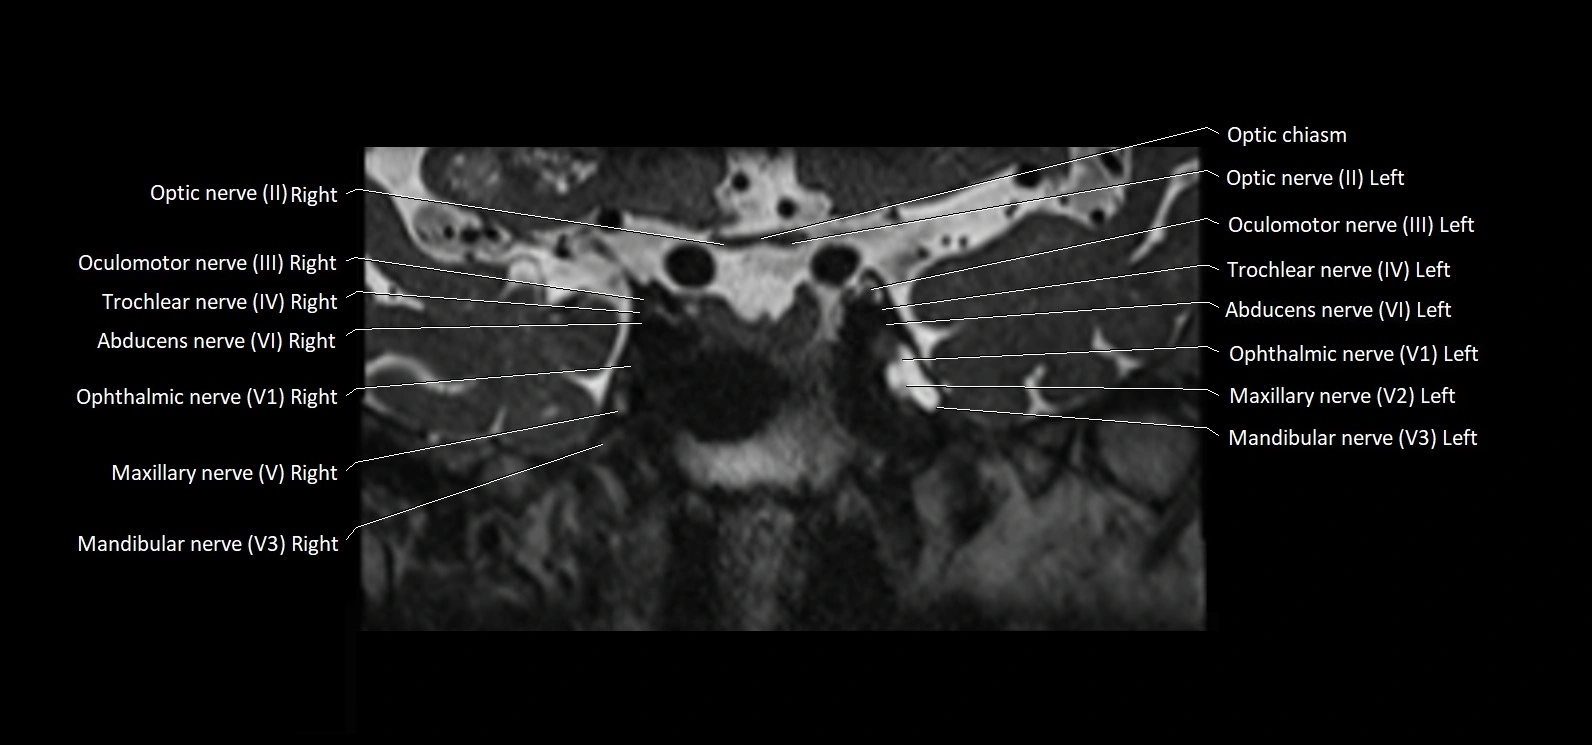

MRI Appearance

• The abducens nerve is a small, thin, linear structure

• Best visualized on high-resolution T2-weighted 3D MRI sequences (e.g., FIESTA or CISS)

• Seen as a hypointense (dark) line running from the brainstem at the pontomedullary junction, traversing the prepontine cistern, and entering Dorello’s canal under the petrosphenoidal ligament, then into the cavernous sinus, and finally the orbit

• May be challenging to visualize in standard MRI due to its small size

• Pathology may be inferred by absence, displacement, or enhancement of the nerve

MRI images

image